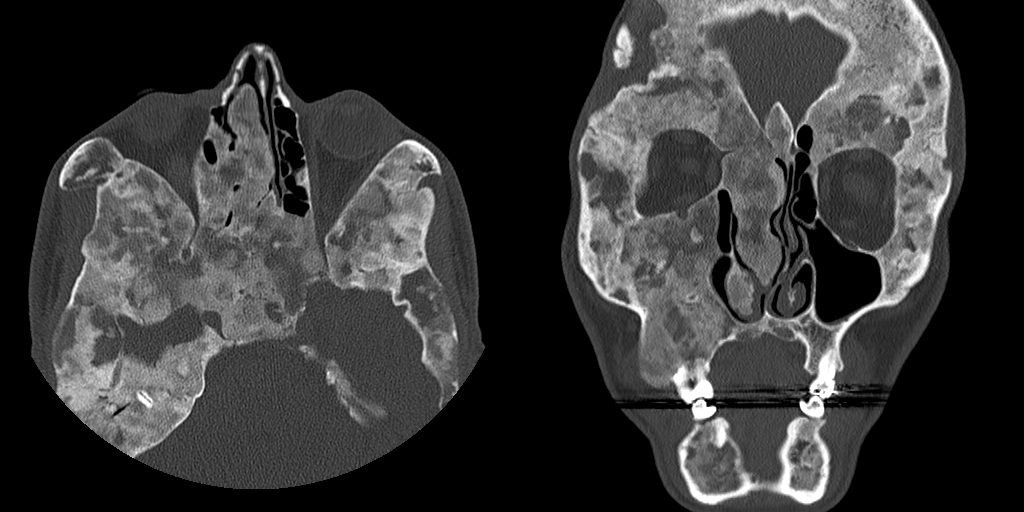

侵犯颅骨者表现头颅或颜面不对称、突眼等,称 「 骨性狮面 」。

注:颅底骨(颞骨鳞部、右侧蝶骨体、蝶骨大翼、右侧筛窦壁)膨大,呈磨玻璃样改变,右侧翼管、圆孔变窄。T1WI 呈低信号,T2WI 呈低信号,增强 T1WI 呈轻度不均匀强化。